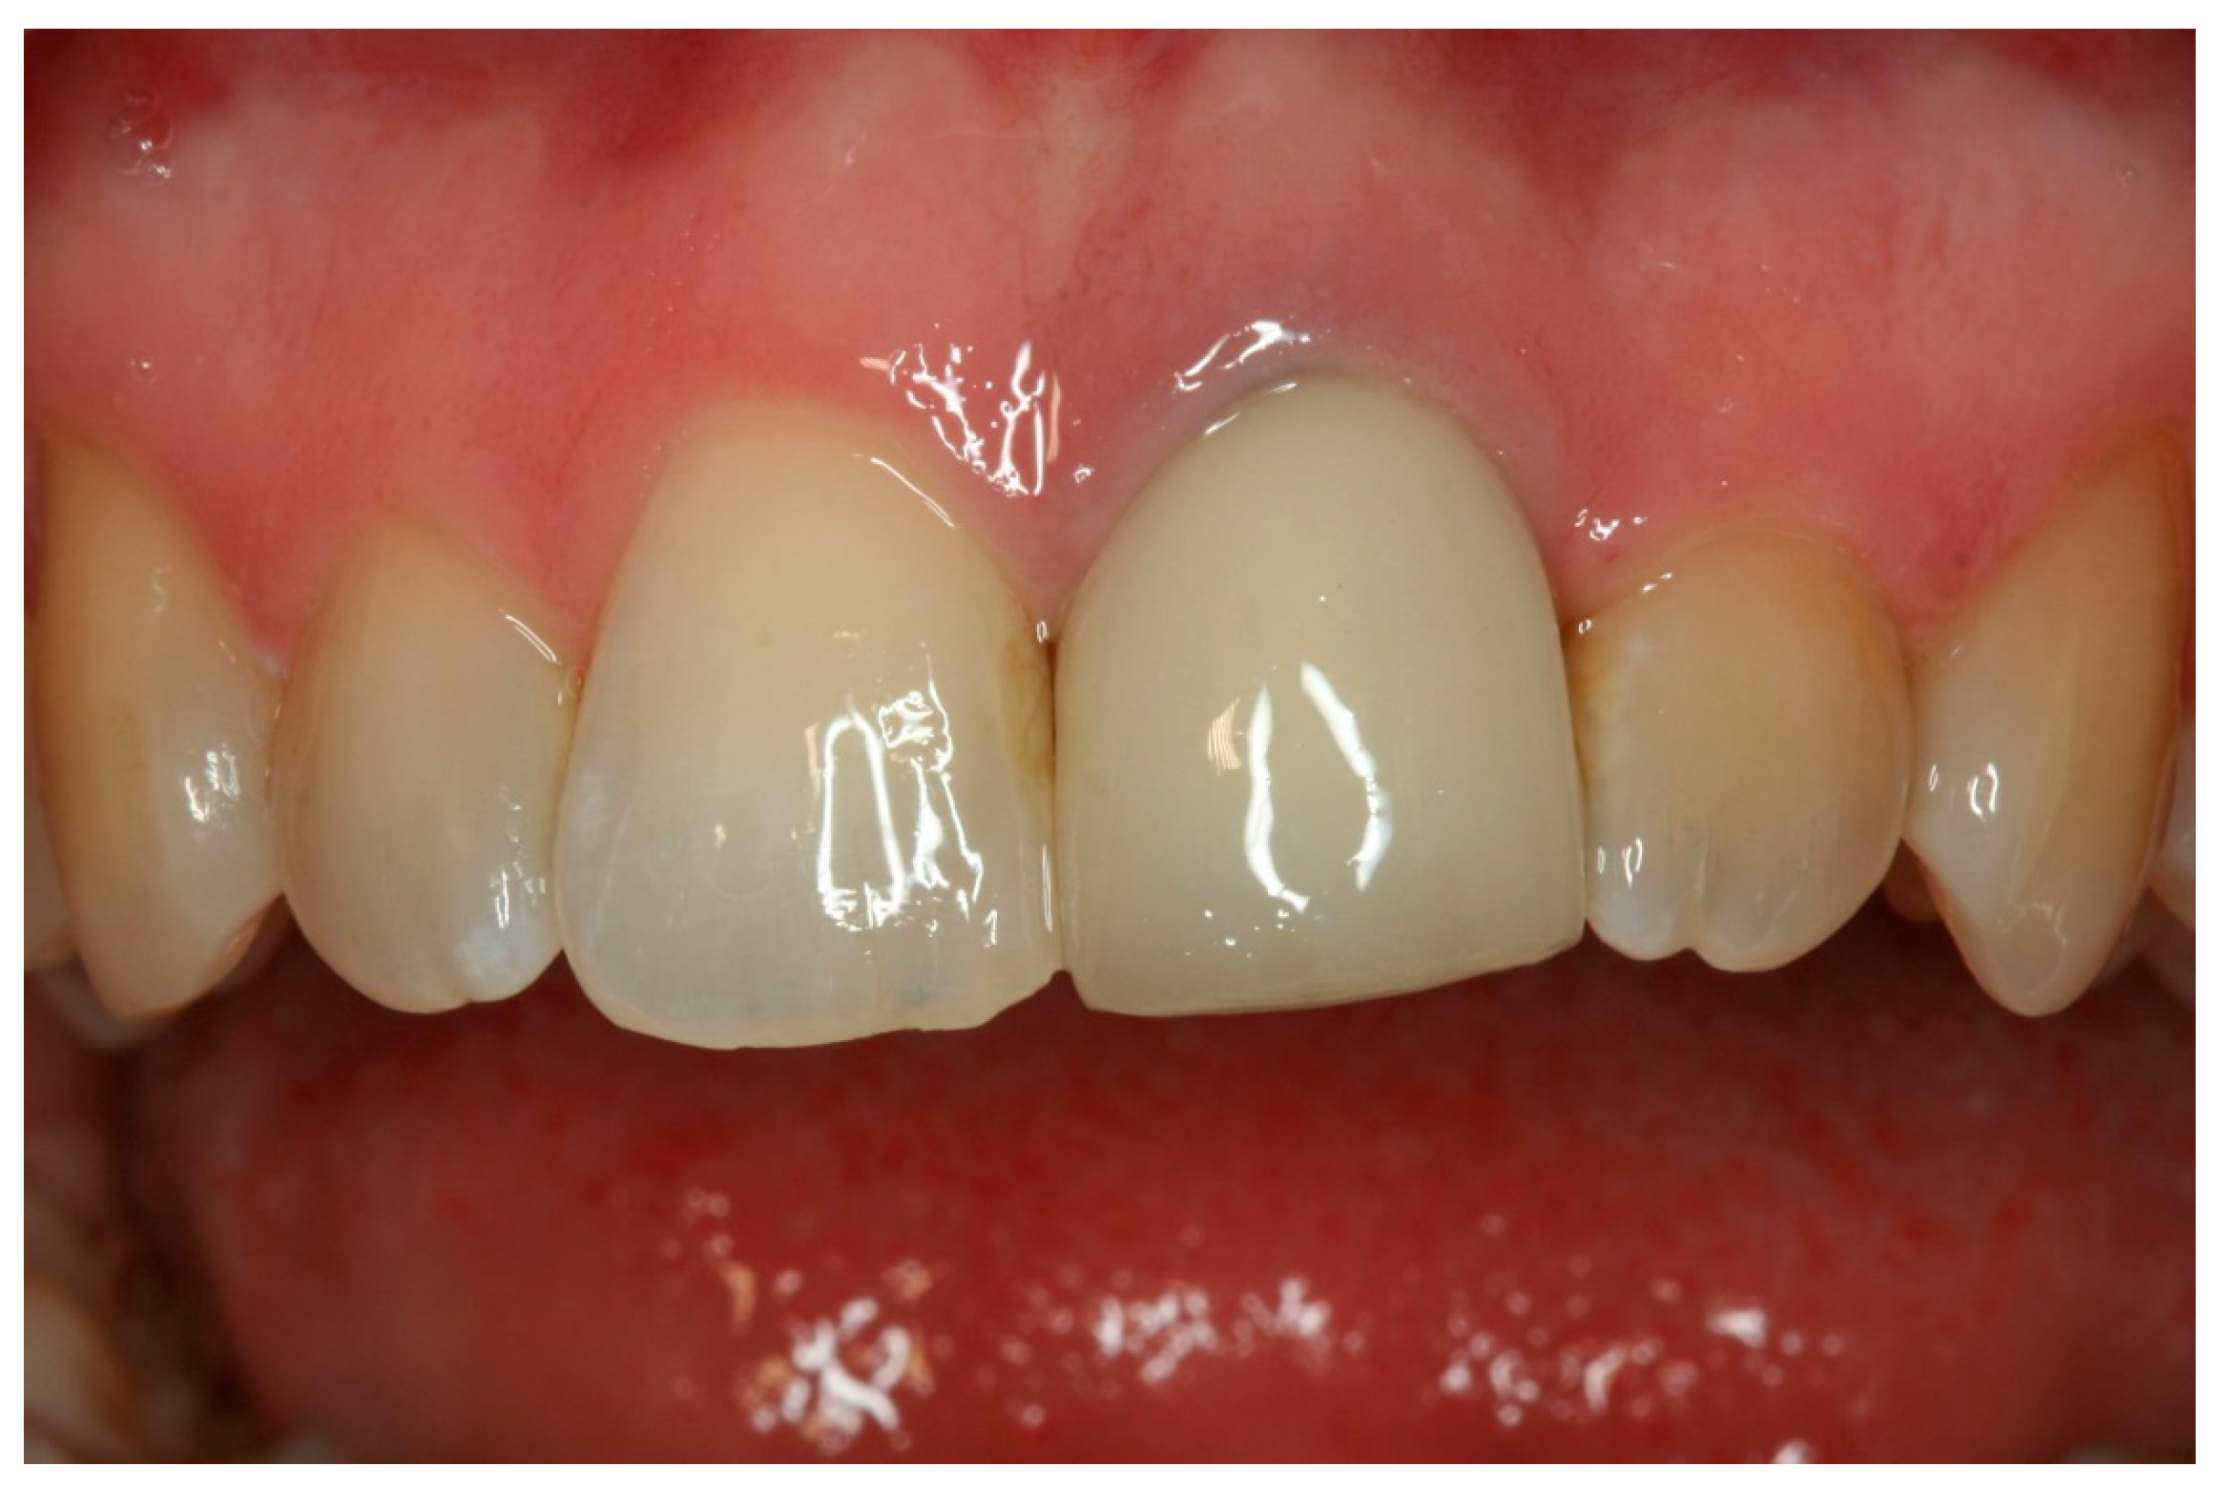

A 57-year-old female was referred in August 2009 to a periodontal specialist practice in Brisbane, Australia with a failing upper left central incisor. Upon examination, it was observed that tooth 21, which was previously root canal treated, had suffered a vertical root fracture and was deemed unrestorable with a hopeless prognosis (Figure 1).

Figure 1.

Preoperative presentation: Failing 21.